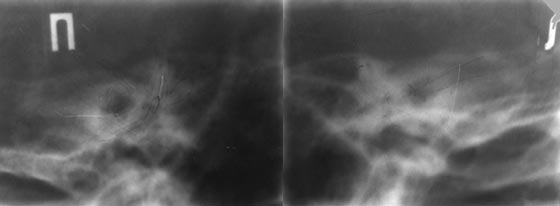

Рис. 1. Невринома слухового нерва. На рентгенограмме вичочной кости в проекции Стенверса имеется расширение внутреннего слухового прохода справа.